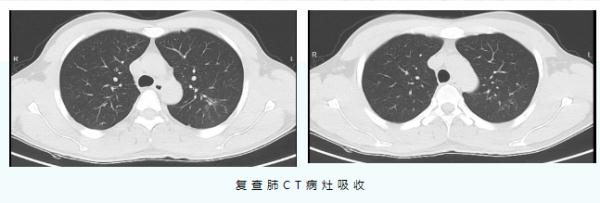

经过中西医结合对症治疗10天后,肺部CT等检查提示,患者的肺炎较之前明显吸收,目前已好转出院。

据介绍,这名男子发热咳嗽3天后来到宁波市中医院就诊。当时他的体温达到39℃,肺部CT显示左肺有大片炎症。